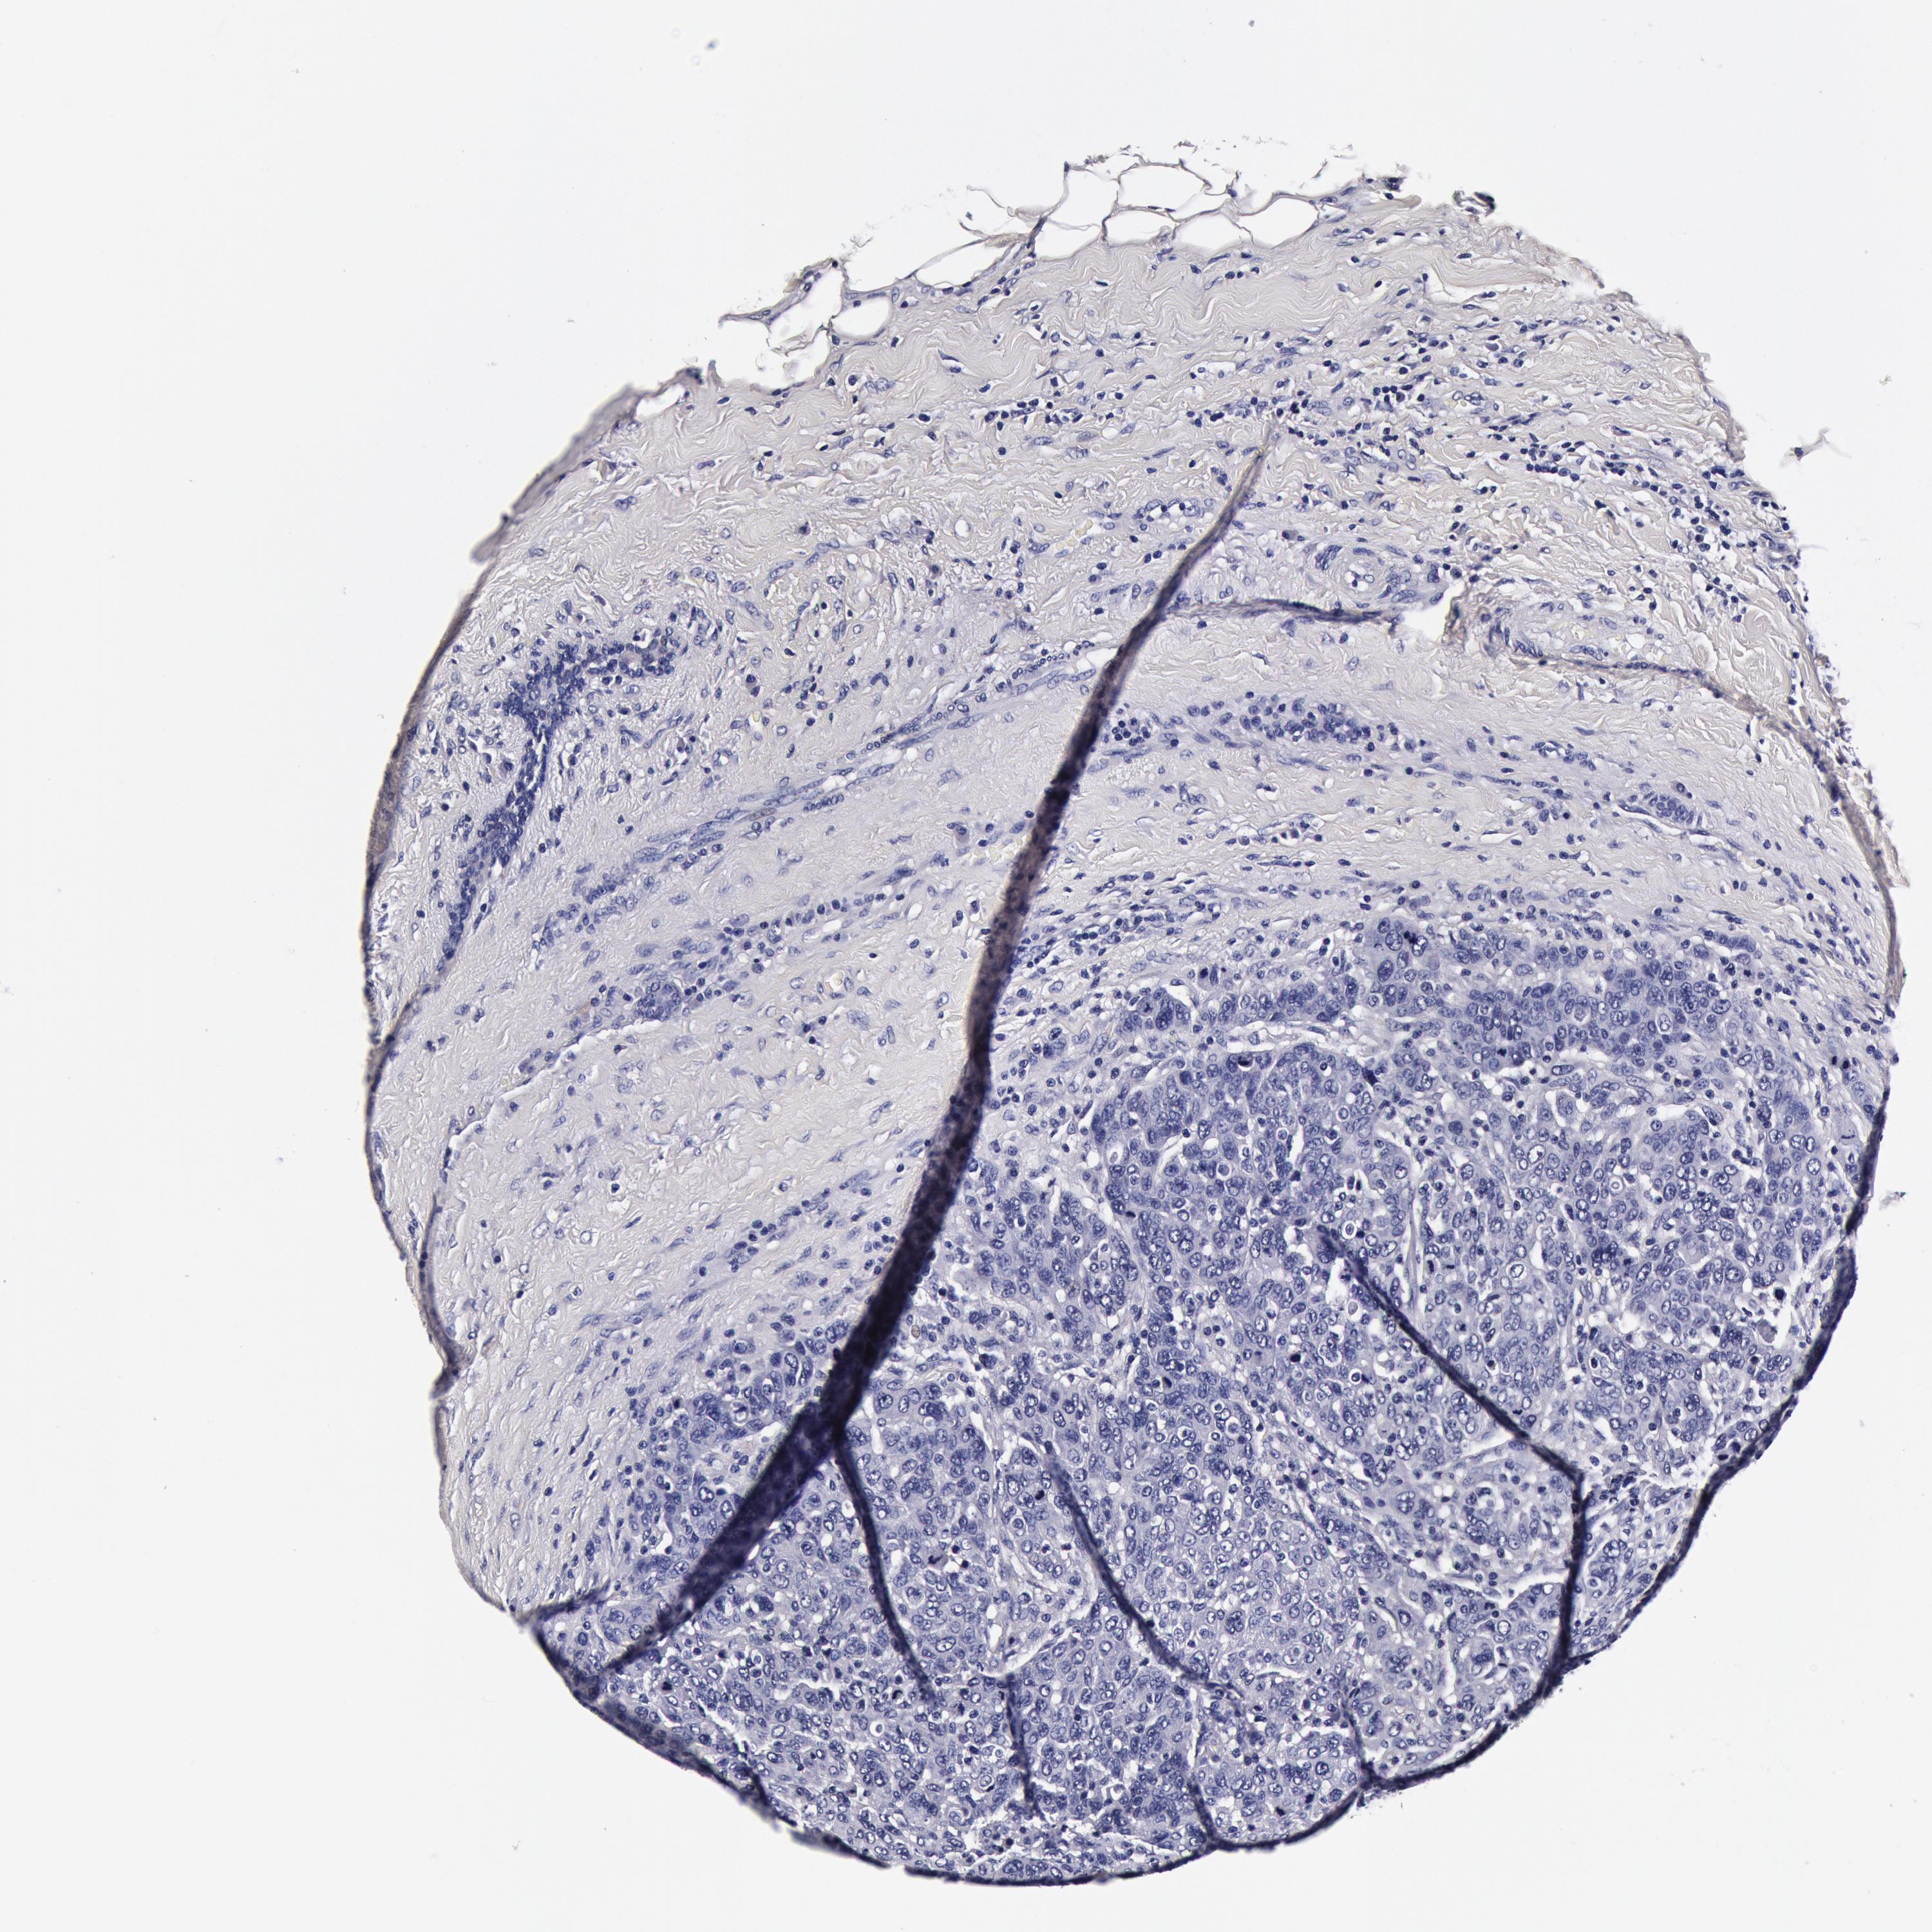

Breast cancer

Human cancer